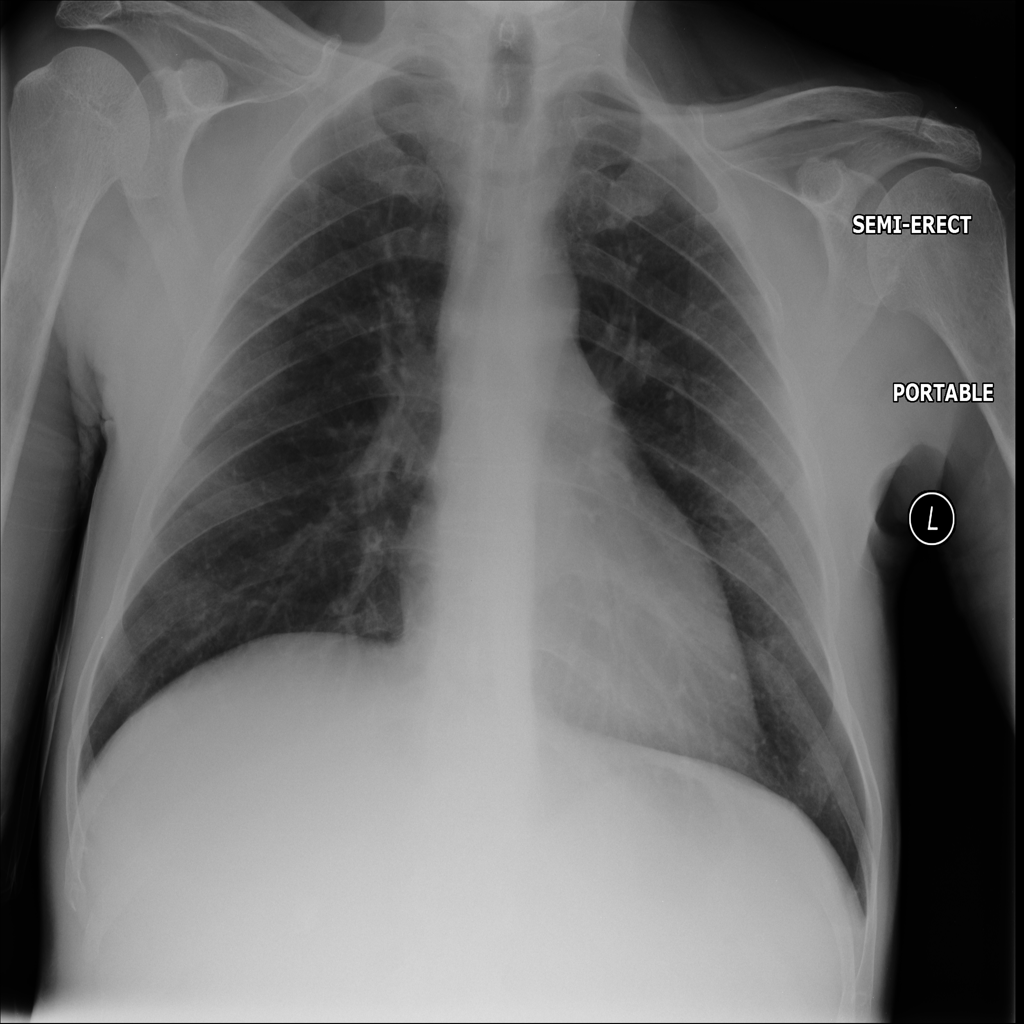

PAT-A1E2 · IMG-001Pneumonia

PAT-A1E2 · IMG-001

AP